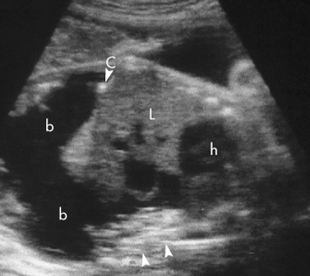

Fetal ascites